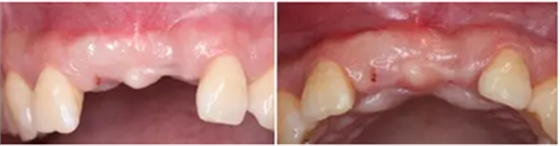

患者33歲,女性,主訴4個(gè)月前因外傷拔除上11、21牙,未行活動(dòng),固定義齒修復(fù),現(xiàn)因影響美觀要求種植修復(fù)。11,21牙缺失,缺牙區(qū)牙齦狀況良好,無(wú)潰瘍紅腫,厚齦型,口腔衛(wèi)生較好,無(wú)明顯牙齦退縮。

CBCT檢查顯示:水平向骨量不足,無(wú)明顯垂直向骨缺損。